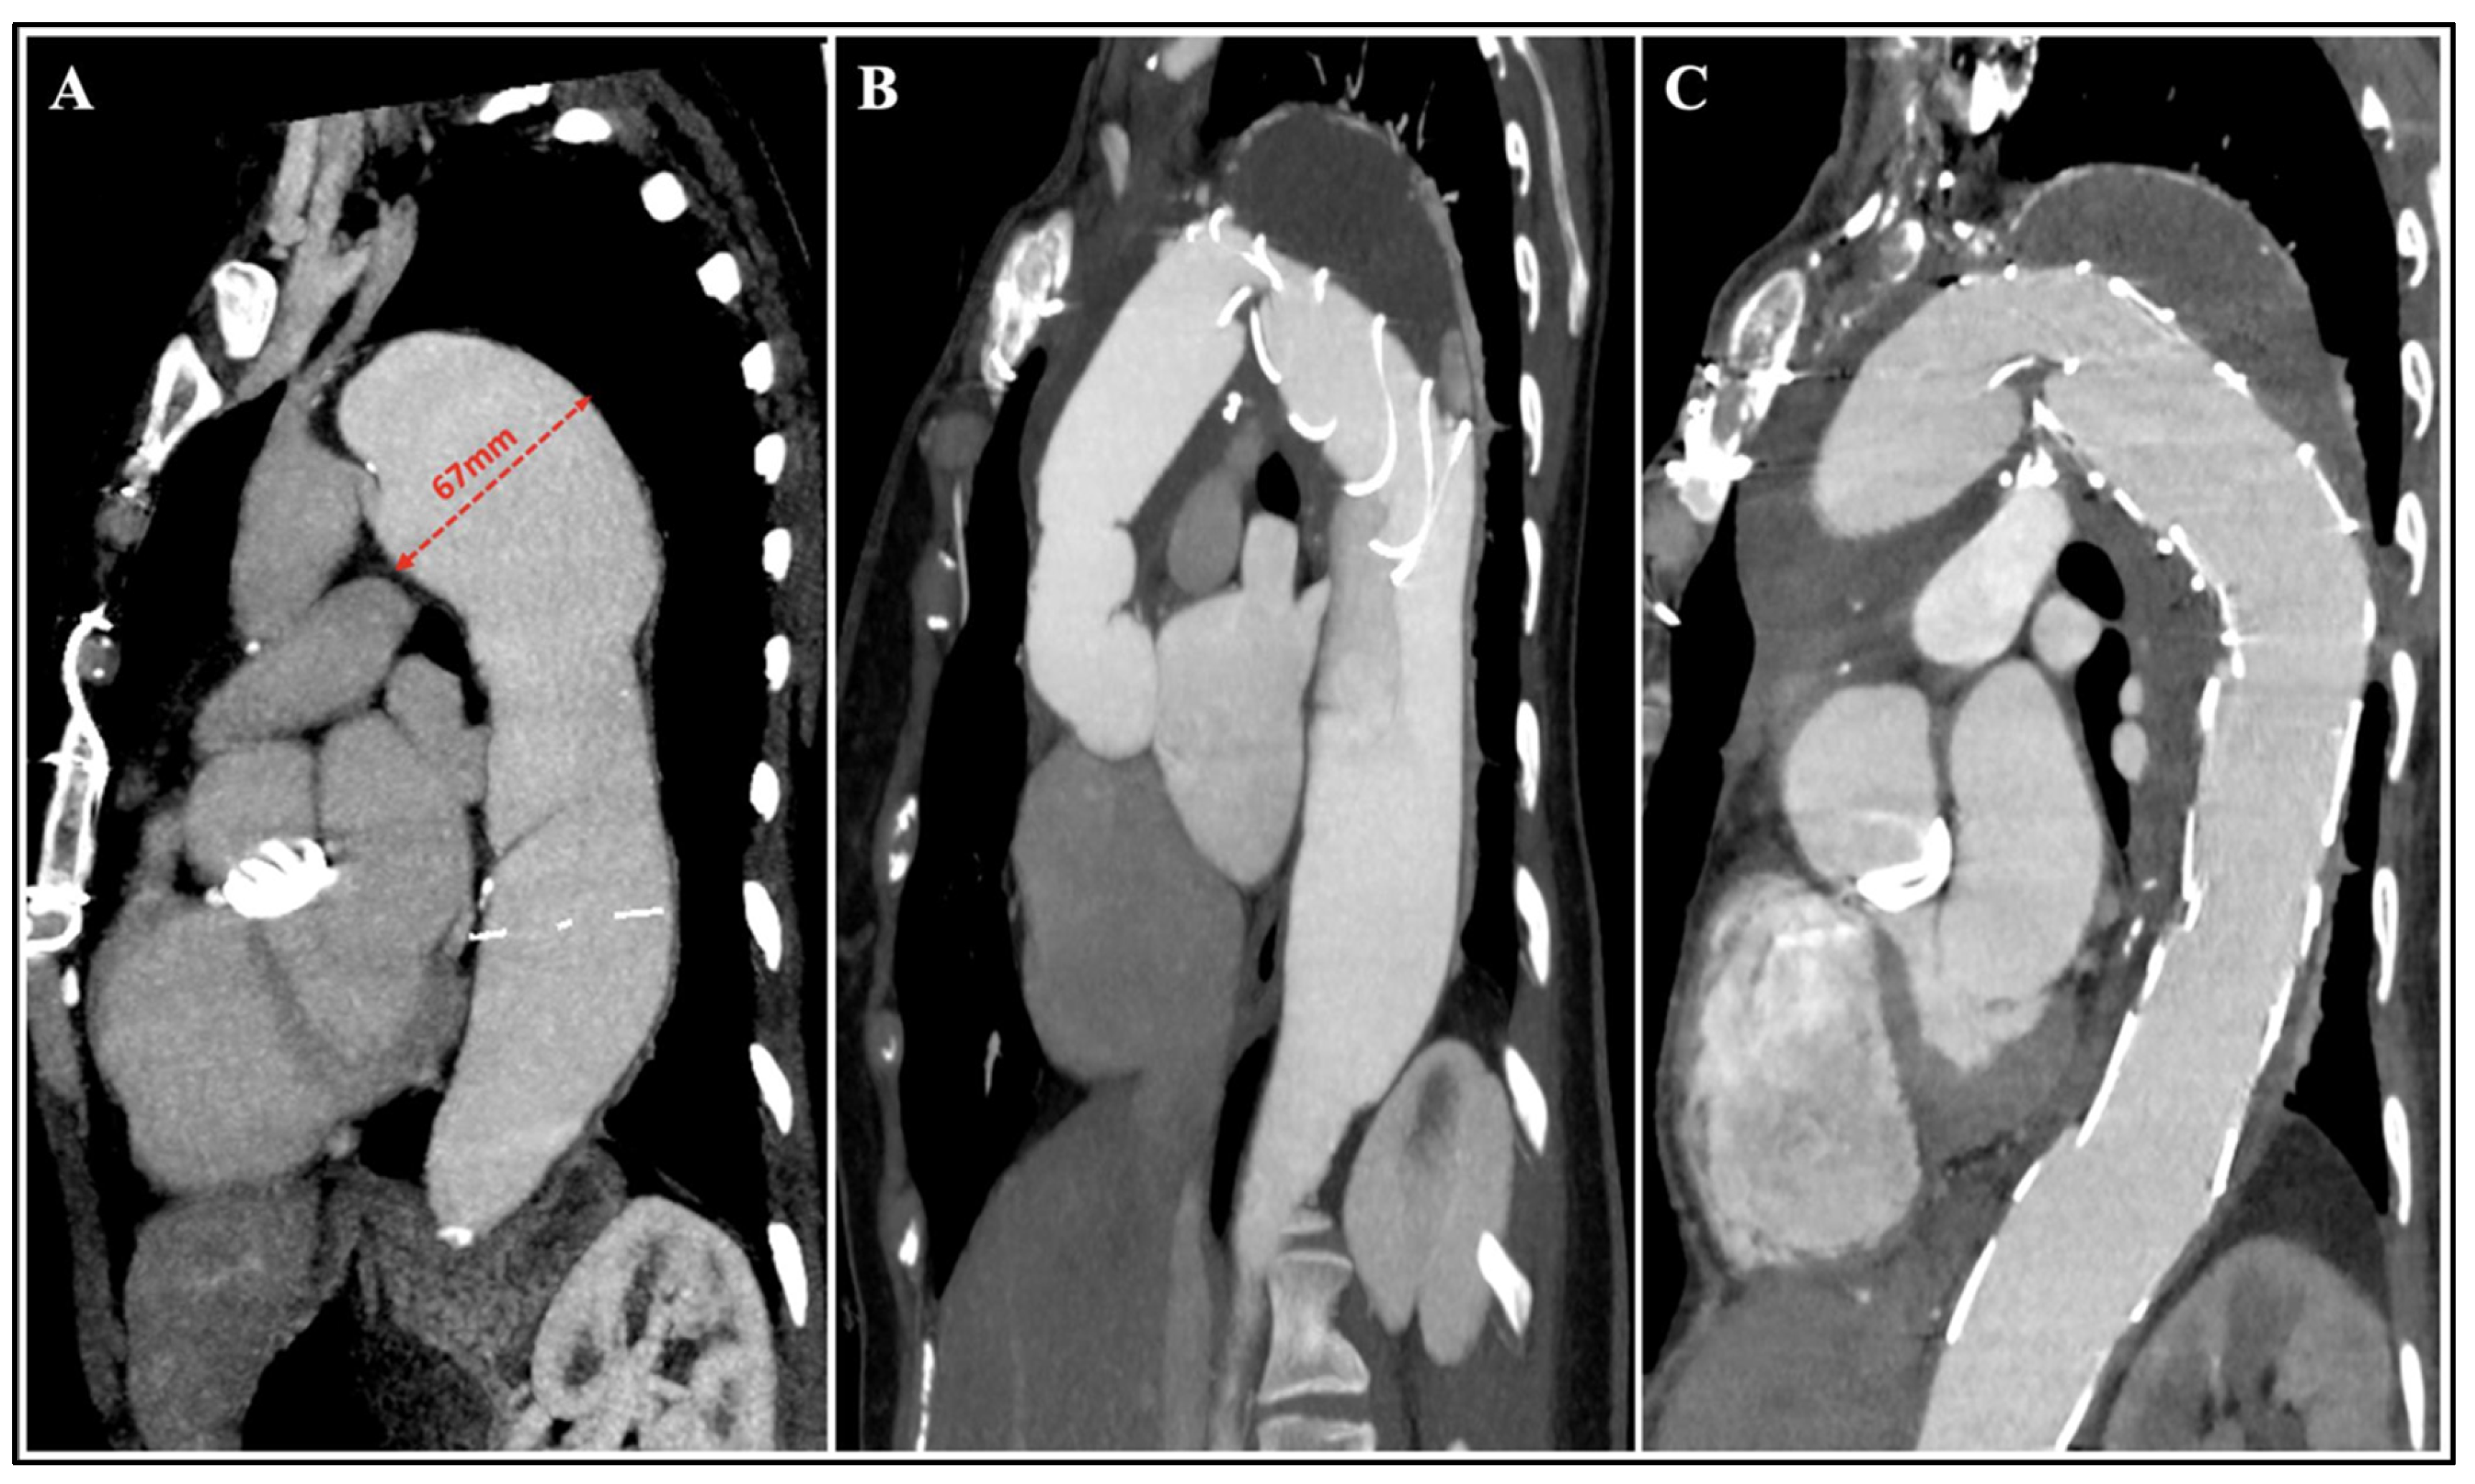

4.1. Procedural Planning and Stent-Graft Selection